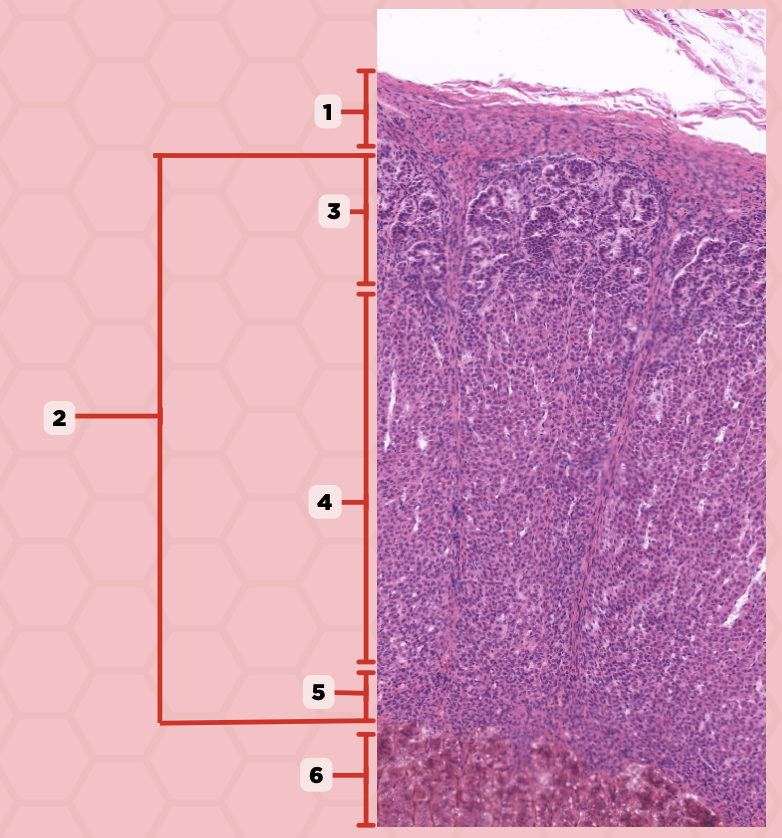

Parathyroid

Identify the specimen.

Chief Cells

Identify the structure labeled as 1. This comprise the majority of cells in the parathyroid gland.

Septa

Identify the structure labeled as 2.

Parathyroid hormones

What hormones are synthesized and secreted by the cell in Pointer #1?

Oxyphil cells

What parenchymal cells in the parathyroid gland only appear shortly before puberty and increase in number with age?